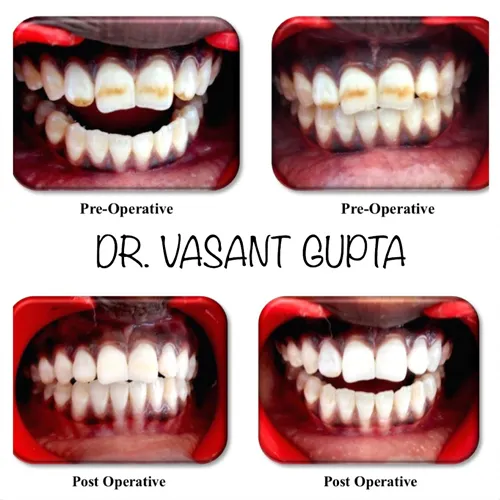

DR. VASANT GUPTA

VENEERS & CROWNS

Both veneers and crowns can improve your smile and the function of your teeth.

I am putting this review after 2 years. I had got veneering done at that time. The teeth shines as it used to be on first day. Highly satisfied with the treatment. Highly recommended.